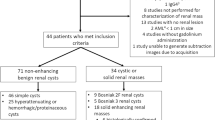

Three radiologists [Reader A (**), B (**), and C (**), with 9, 11, and 14 years of clinical experience in genitourinary MR imaging, respectively] independently reviewed the FSE MRU and GRASE MRU images on the picture archiving and communication system (PACS) with a 2-week interval to minimize recall bias. The source and MIP images were anonymized and arranged randomly without information on acquisition methods. The readers were free to adjust the window settings according to the reader's experience. The flowchart of the study is demonstrated in Fig. 2.

Among 114 participants, 24 patients were excluded (Fig. 2). Finally, 90 patients (47 men and 43 women; mean age, 49.3 ± 19.1 years; ranges, 18–87 years) were included. The reference standard for the diagnosis of urinary tract pathology was based on subsequent surgery (n = 22) and endoscope (n = 22). Of these, 21 were diagnosed with malignant lesions and 23 had benign strictures. The remaining 46 patients were clinically diagnosed due to benign considerations based on clinical information, imaging analysis, and laboratory findings (Table 1).